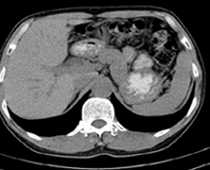

患者,男,57,常年不吃午饭,近一个月来腹部隐痛,无明显黄疸,明天进行增强扫描,图象另上传,麻烦各位帮忙一起看看讨论讨论

肝外胆管扩张,胰头增大,肠系膜上静脉似有包埋征象。

考虑:胰头占位性病变,建议增强进一步检查。

肝外胆管稍扩张,胰腺钩突略增大,但外形尚可,境界清楚。(常年不吃午饭)提示胰腺炎可能大,肿瘤第二步考虑。

支持考胰头占位性病变,感觉十二指肠壁不规则增厚,不排除十二指肠降部占位可炎症

胰头增大,胆总管增宽,考虑胰头癌可能性大,明天看增强片有助诊断.